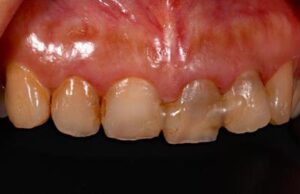

前歯3本欠損症例

前歯3本欠損症例 BEFORE AFTER 46歳女性/上3本欠損/インプラント埋込手術 【治療内容】 前歯3本に根尖病…